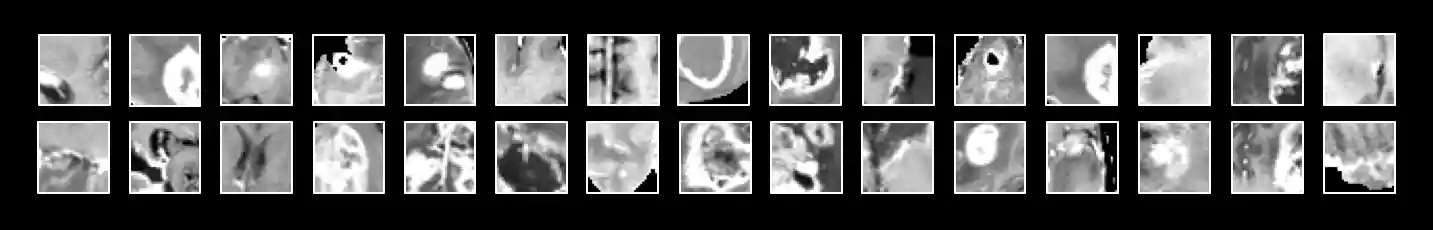

The purpose of training the model on patches (Figure 8) is to exploit the fact that a class of any given voxel is highly dependent on the class of it's surrounding voxels. Patches give the net access to information about the pixel's local environment, which influences the final prediction of the patch.

Figure 8: Examples of 33 x 33 pixel patches used as input for the neural network. These particular patches were acquired with a T1C pulse sequence, but the actual input includes all pulse sequences.Another important factor in patch selection is to make sure the classes of the input data are balanced. Otherwise, the net will be overwhelmed with background images and fail to classify any of the minority classes. Approximately 98% of the data belongs to the background class (healthy tissue or the black surrounding area), with the remaining 2% of pixels divided among the four tumor classes.